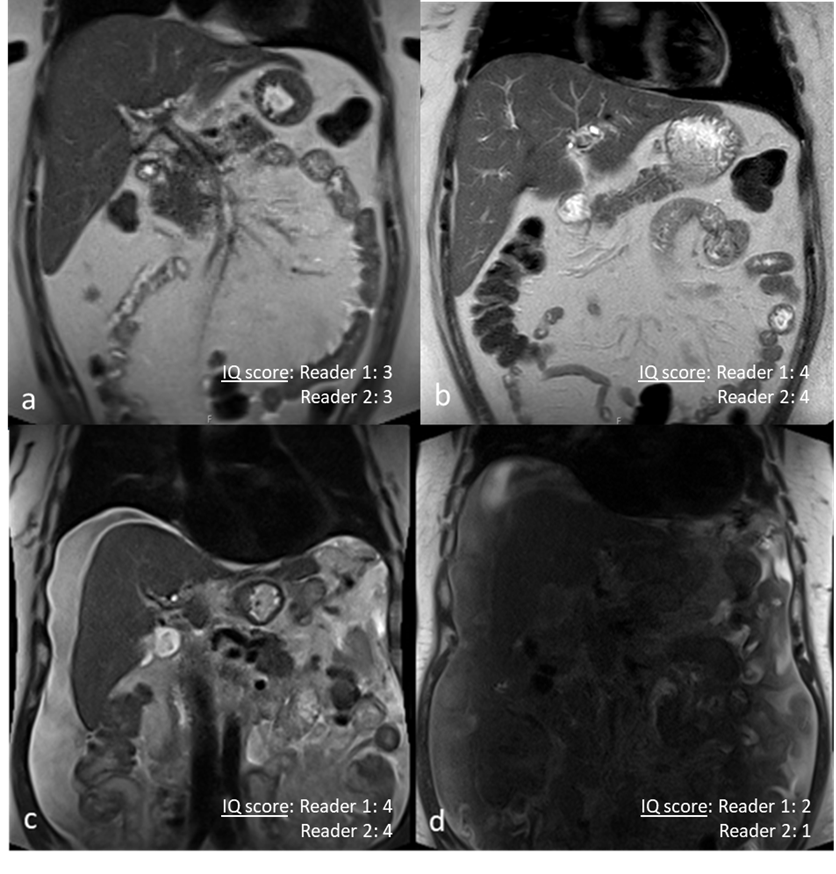

Comparison of 0.55T and 1.5T in 2 patients. Coronal SS T2w TSE in a patient Primary Sclerosing Cholangitis at 0.55T(a) and 1.5T(b). Because of low SNR on 0.55T, lower IQ score were assigned by both readers to (a) compared to (b). Coronal SS T2w TSE in another patient with ascites at 0.55T(c) and 1.5T (d). There is central signal loss at 1.5T(d) resulting in a lower rating on 1.5T(d) compared to 0.55T(c)